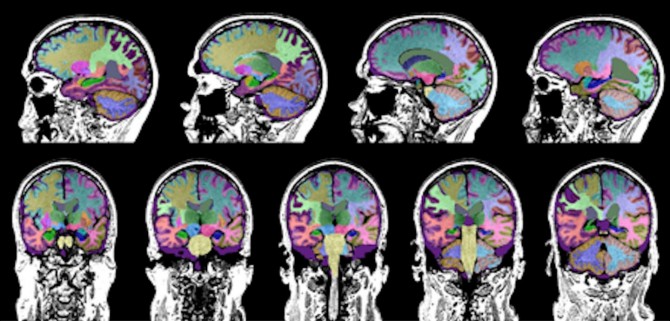

A software program quantifies brain volume in study participants with TBI. (Credit: UCLA Health)

Using a software program to analyze the MRI scans, the study revealed that TBI caused the most damage to a brain region known as the ventral diencephalon, with the least amount of atrophy occurring in the hippocampus, said study author Dr. Cyrus Raji, an assistant professor of radiology at Washington University in St. Louis. The ventral diencephalon is associated with learning and emotions, whereas the hippocampus is involved in memory and emotions. The hippocampus also is the region of the brain that is most impacted by Alzheimer's disease.